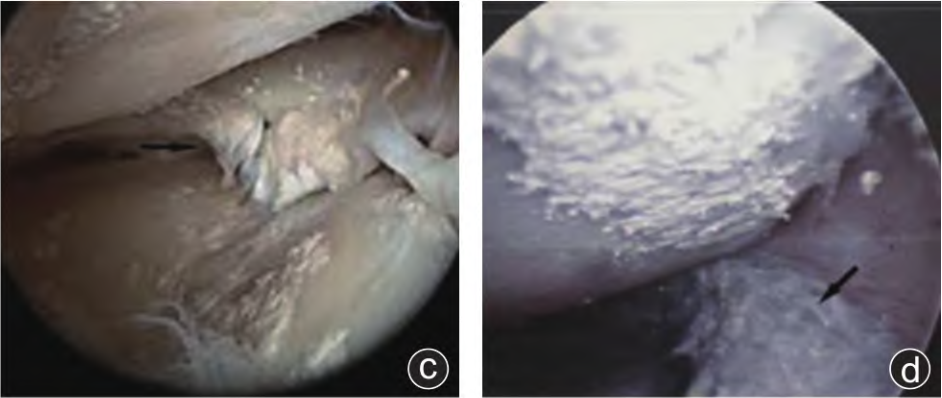

典型病例見(jiàn)圖1。

圖1 病人,男,38歲,因左膝關(guān)節(jié)腫痛、活動(dòng)受限1年,加劇1個(gè)月入院。入院診斷為“左膝關(guān)節(jié)痛風(fēng)性關(guān)節(jié)炎”,WOMAC評(píng)分:53分,Kellgren?Lawrence分級(jí):I級(jí),行左膝關(guān)節(jié)關(guān)節(jié)鏡下高頻脈沖沖洗術(shù)。

股骨髁(a)、脛骨平臺(tái)關(guān)節(jié)面(b)附著痛風(fēng)石結(jié)晶,

半月板(c)、前交叉韌帶(d)、滑膜(e)形成痛風(fēng)石伴組織破壞。